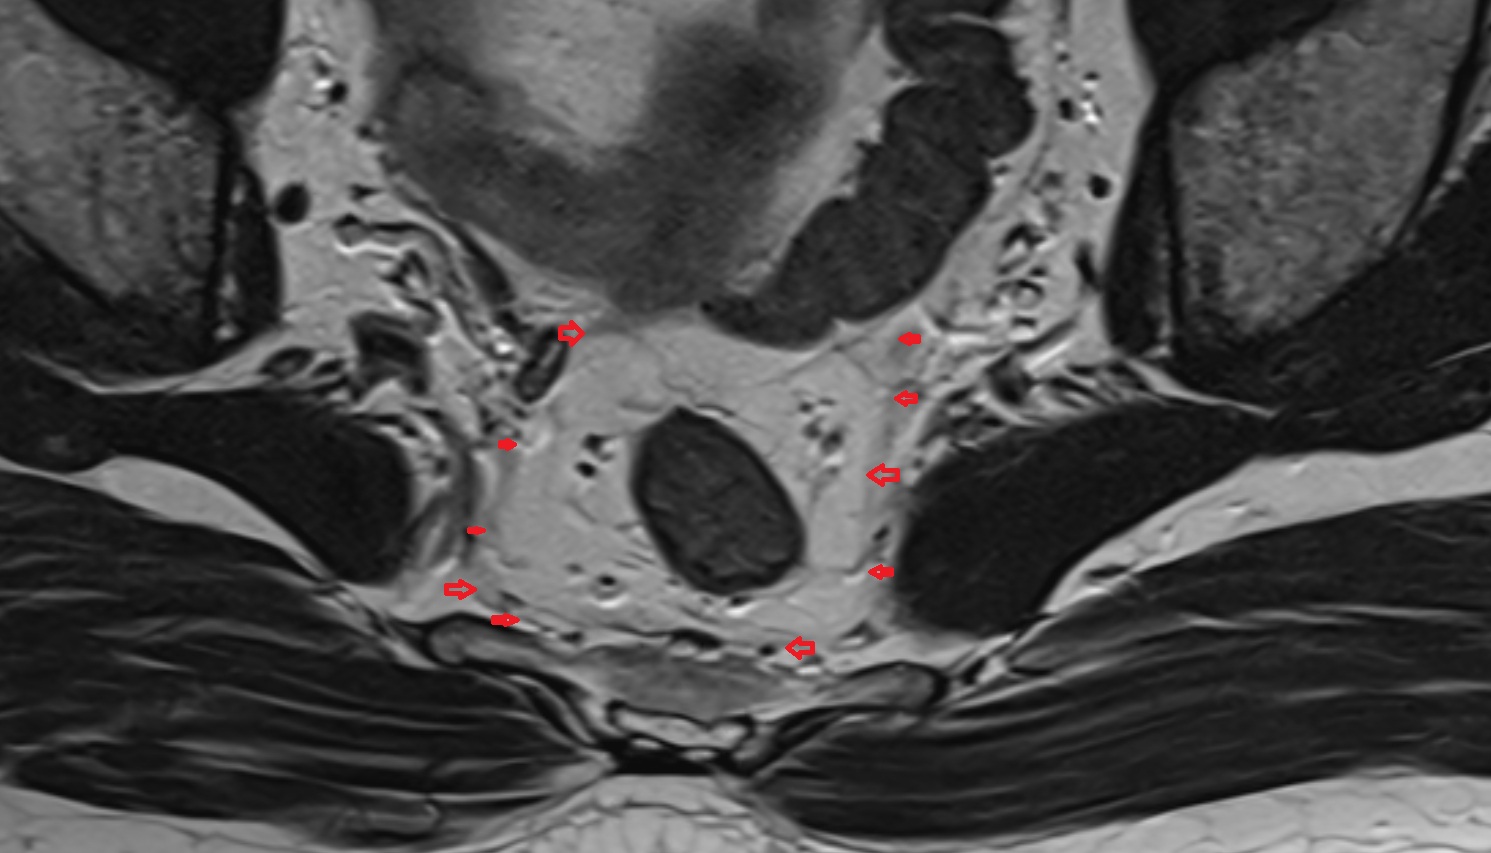

- Mesorectal fascia

- Mesorectum

- Rectum